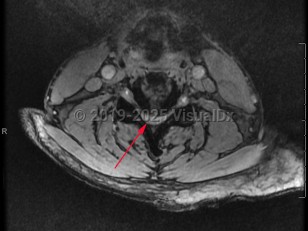

Cervical spinal stenosis

Cervical spinal stenosis is the narrowing of the spinal canal in the neck. Asymptomatic spinal stenosis may be discovered incidentally on imaging, but when it causes impingement of the spinal cord or nerve roots, symptoms can include weakness of the extremities, numbness / paresthesias, and neuropathic / radicular pain.

Spinal stenosis can be congenital, but more typically it is acquired. It most frequently presents in the sixth decade of life or later due to degenerative changes to the spine that result in progressive narrowing of the spinal canal and/or neural foramina. It is also possible that people with congenitally narrow spinal canals are more likely to experience symptoms during the process of aging. Other risk factors for the development of spinal stenosis include inflammatory arthropathies such as rheumatoid arthritis, traumatic injuries, and neoplastic disease.